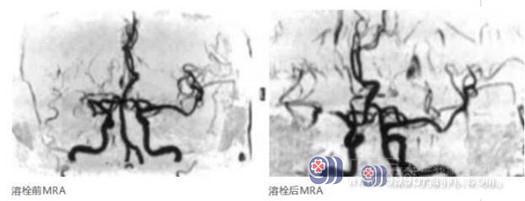

到达医院后,主管医生潘梦秋主治医生立即完善相关检查。查体:双眼向右侧凝视,左侧鼻唇沟变浅,伸舌左偏,构音不清,四肢肌张力正常,左上肢肌力4级,左下肢肌力3-级。我院DWI提示右侧颞叶、基底节-放射冠区急性脑梗塞;MRA提示右侧大脑中动脉闭塞。

经综合评估,患者具有静脉溶栓指征,无相关禁忌症。在告知患者家属病情及溶栓风险,并取得知情同意后,决定予以rt-PA静脉溶栓治疗。溶栓后1小时,患者症状得到改善,NIHSS评分由7分降为4分,但复查MRA,检查结果提示右侧大脑中动脉部分显影,考虑患者右侧大脑中动脉仍存在狭窄。

为减少血管再闭塞风险,考虑桥接介入取栓治疗,经告知患者家属介入治疗必要性及相关风险,家属知情同意后,即予以介入治疗。

术中将Solitaire SAB-4-20支架释放于大脑中动脉狭窄处,造影显示闭塞段血管复流,远端血管显影通畅。随后将支架拉出体外,可见支架覆盖有少量血栓,复查造影提示大脑中动脉M1段及大脑中动脉上、下干显影通畅,狭窄处较前好转。